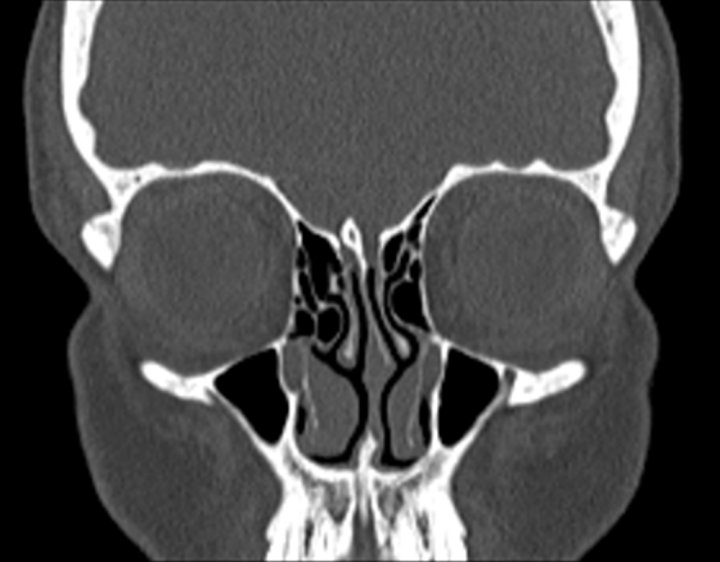

Click any image for labels.